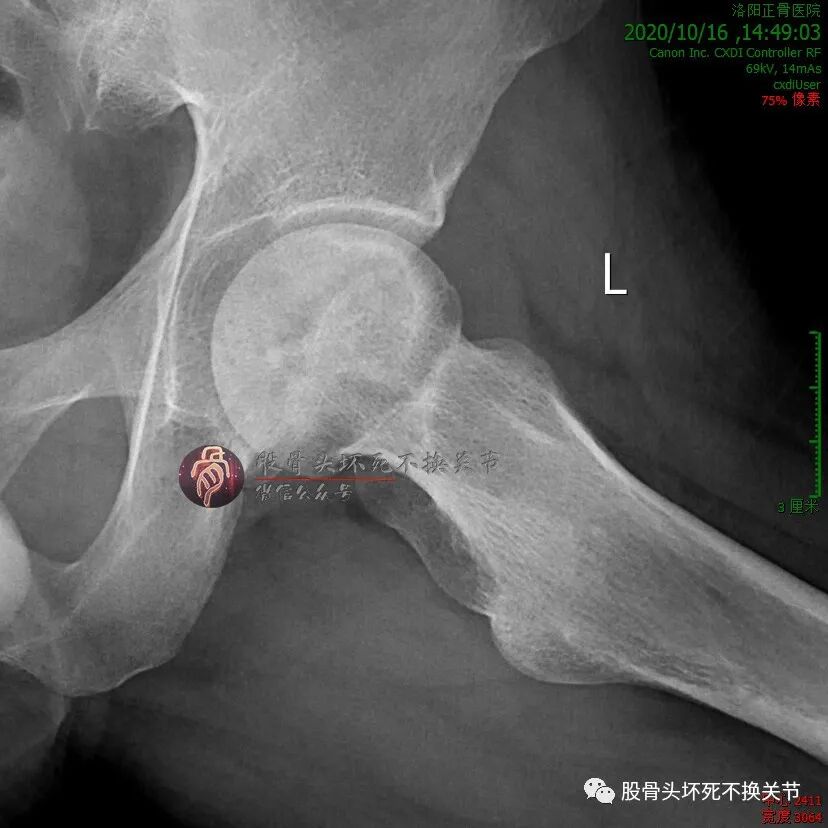

男性,34岁,2019年11月确诊左侧股骨头坏死,2020年1月前来住院行冲击波综合保髋治疗,详情如下:

股骨头内大面积的密度不均减低区就是坏死区。

微创植骨,还是开放植骨?

先别急着决定,看看CT再说:

这个面积,超出了一般微创植骨工具所能及的范围;若开放植骨,则外侧柱会自然而然成为“天然死角”,术后拍片估计要打脸。